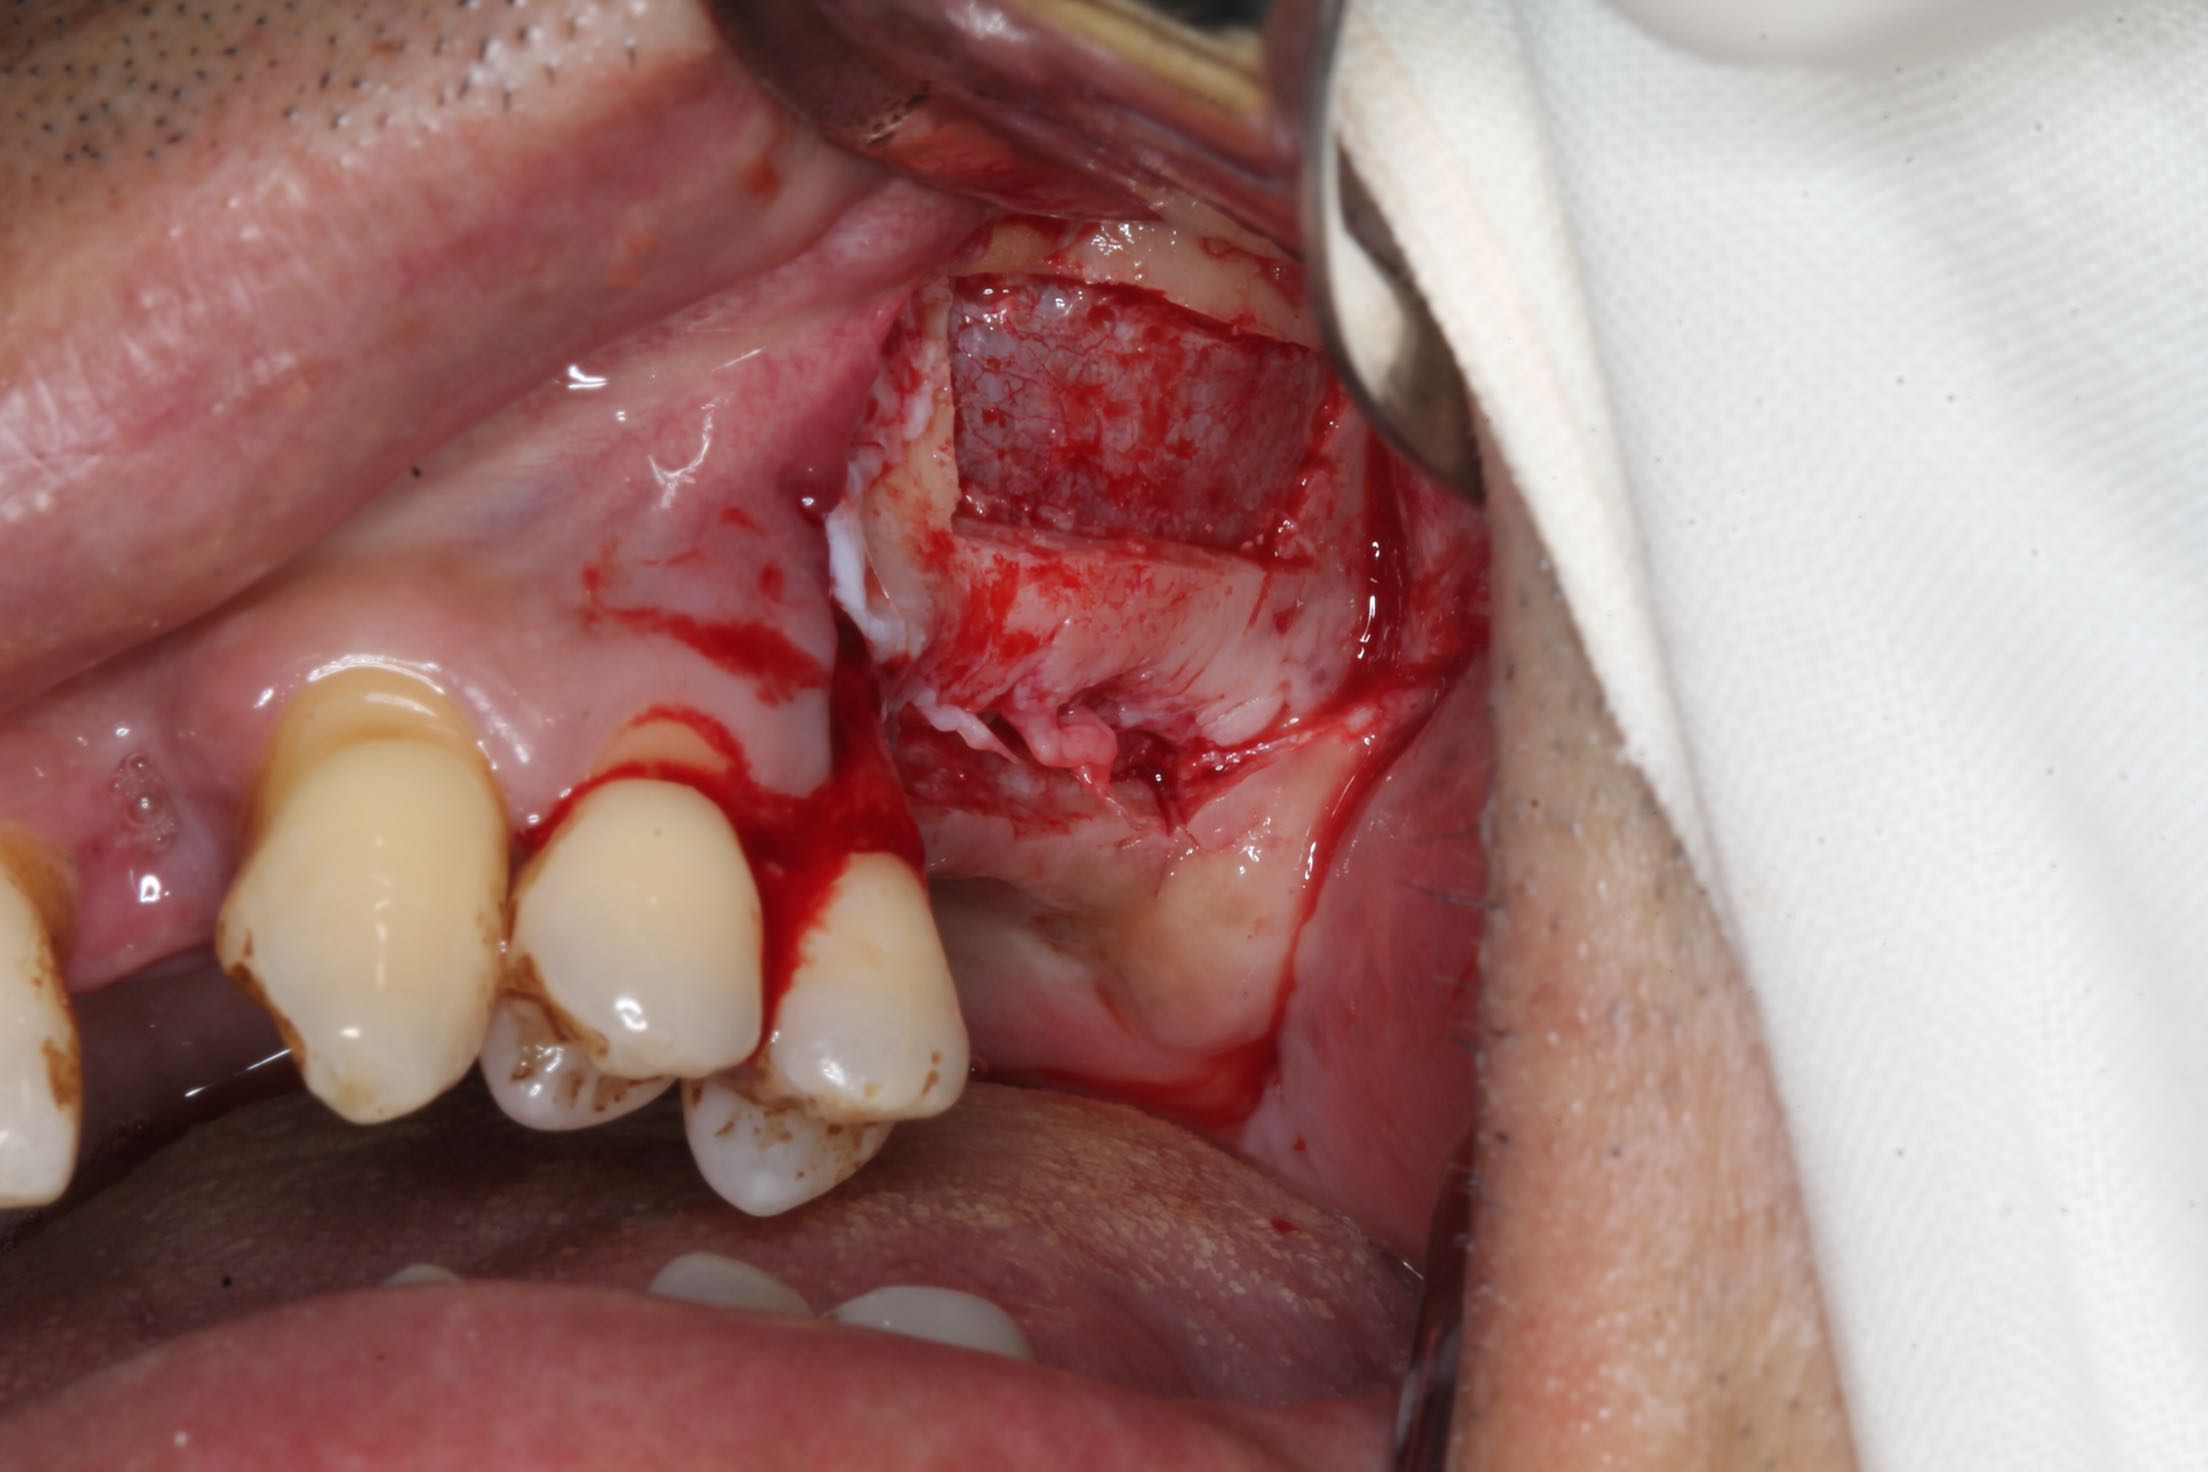

26、27缺失,牙槽骨严重吸收。 治疗:上颌窦外侧壁超刀开窗,取出外侧壁骨块,剥离黏膜,考虑严重吸烟史,黏膜菲薄,垫上一层胶原膜,植入部分Bio-ss骨粉,牙槽嵴顶备洞,26牙植入dentium4.3-10,27牙植入4.3-8,继续植入骨粉共0.5g,开窗处复原骨块,严密缝合!26牙植入扭力35牛,27植入扭力15牛!嘱尽量戒烟,